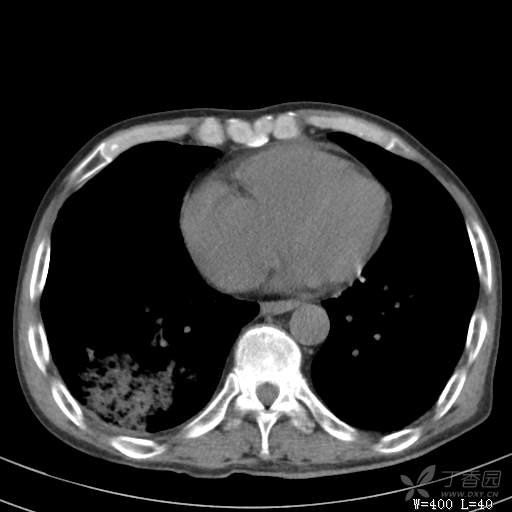

简要病史:主因发热伴腰背部疼痛2小时于2018-06-27,09:30 入院。患者无高血压,冠心病、糖尿病病史,无慢性咳喘史,不吸烟。否认食物药物过敏史。患者于入院前2小时出现发热,体温37.5℃,无咳嗽,咳痰,伴右侧腰背部疼痛,伴呕吐2次,呕吐物为黄绿色胆汁,大便2次,为稀便,无咯血,无胸闷、憋气,无鼻塞、流涕,无尿频、尿急、尿痛,就诊于我院,我院急诊查:上腹部CT:右肾结石,右下肺感染性疾病可考虑,血常规WBC13.54*109/L,GR%45.8%,急诊以“发热待查:肺感染?”收入院。

辅助检查:上腹部CT:右肾结石,右下肺感染性疾病可考虑,血常规:WBC13.54*109/L,GR%45.8%,。心肌酶示:谷草转氨酶12U/L,乳酸脱氢酶328U/L,肌酸激酶20U/L,肌酸激酶同工酶7U/L,α-羟丁酸脱氢酶277U/L,查凝血常规示:凝血酶原时间12.5秒,国际标准化比值1.07,活化部分凝血酶原时间32.6秒,纤维蛋白原浓度1.77g/L,凝血酶时间15.6秒。

临床诊断:1.腰背部疼痛原因待查:1.肺炎?2.泌尿系结石?。

治疗经过:抗感染及止痛对症处理。治疗效果不好,患者腰痛是由什么引起的?